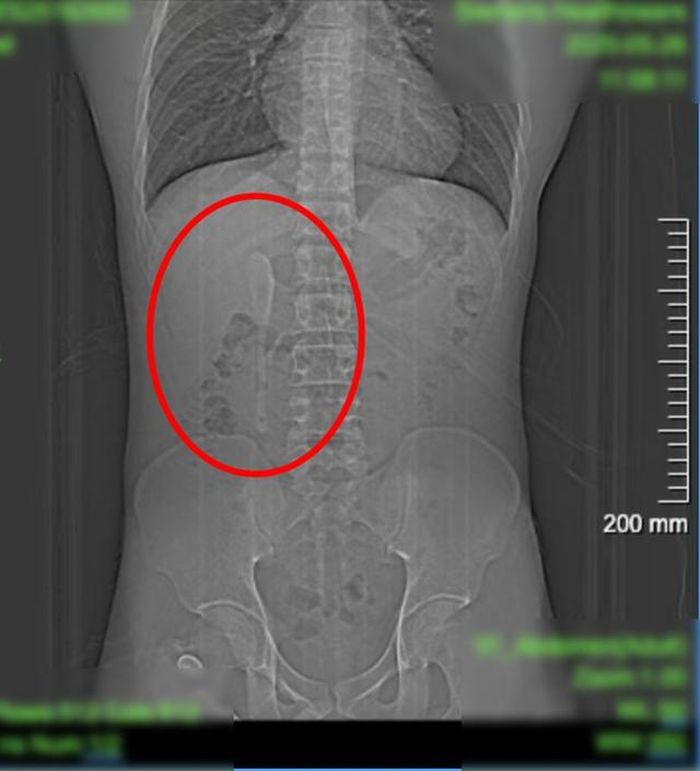

Các bác sĩ đã tiến hành khám sức khỏe và chụp CT để tìm nguyên nhân. Lúc đầu, bệnh nhân nghĩ rằng mình đã vô tình nuốt phải một vật bằng nhựa. Tuy nhiên, những gì họ tìm thấy là một chiếc thìa gốm dài 15 cm mắc kẹt trong tá tràng.

Kết quả chụp CT của người đàn ông cho thấy có một vật thể hình thìa dài gần 15 cm nằm bên trong cơ thể anh ta. Ảnh: Bệnh viện Trung Sơn